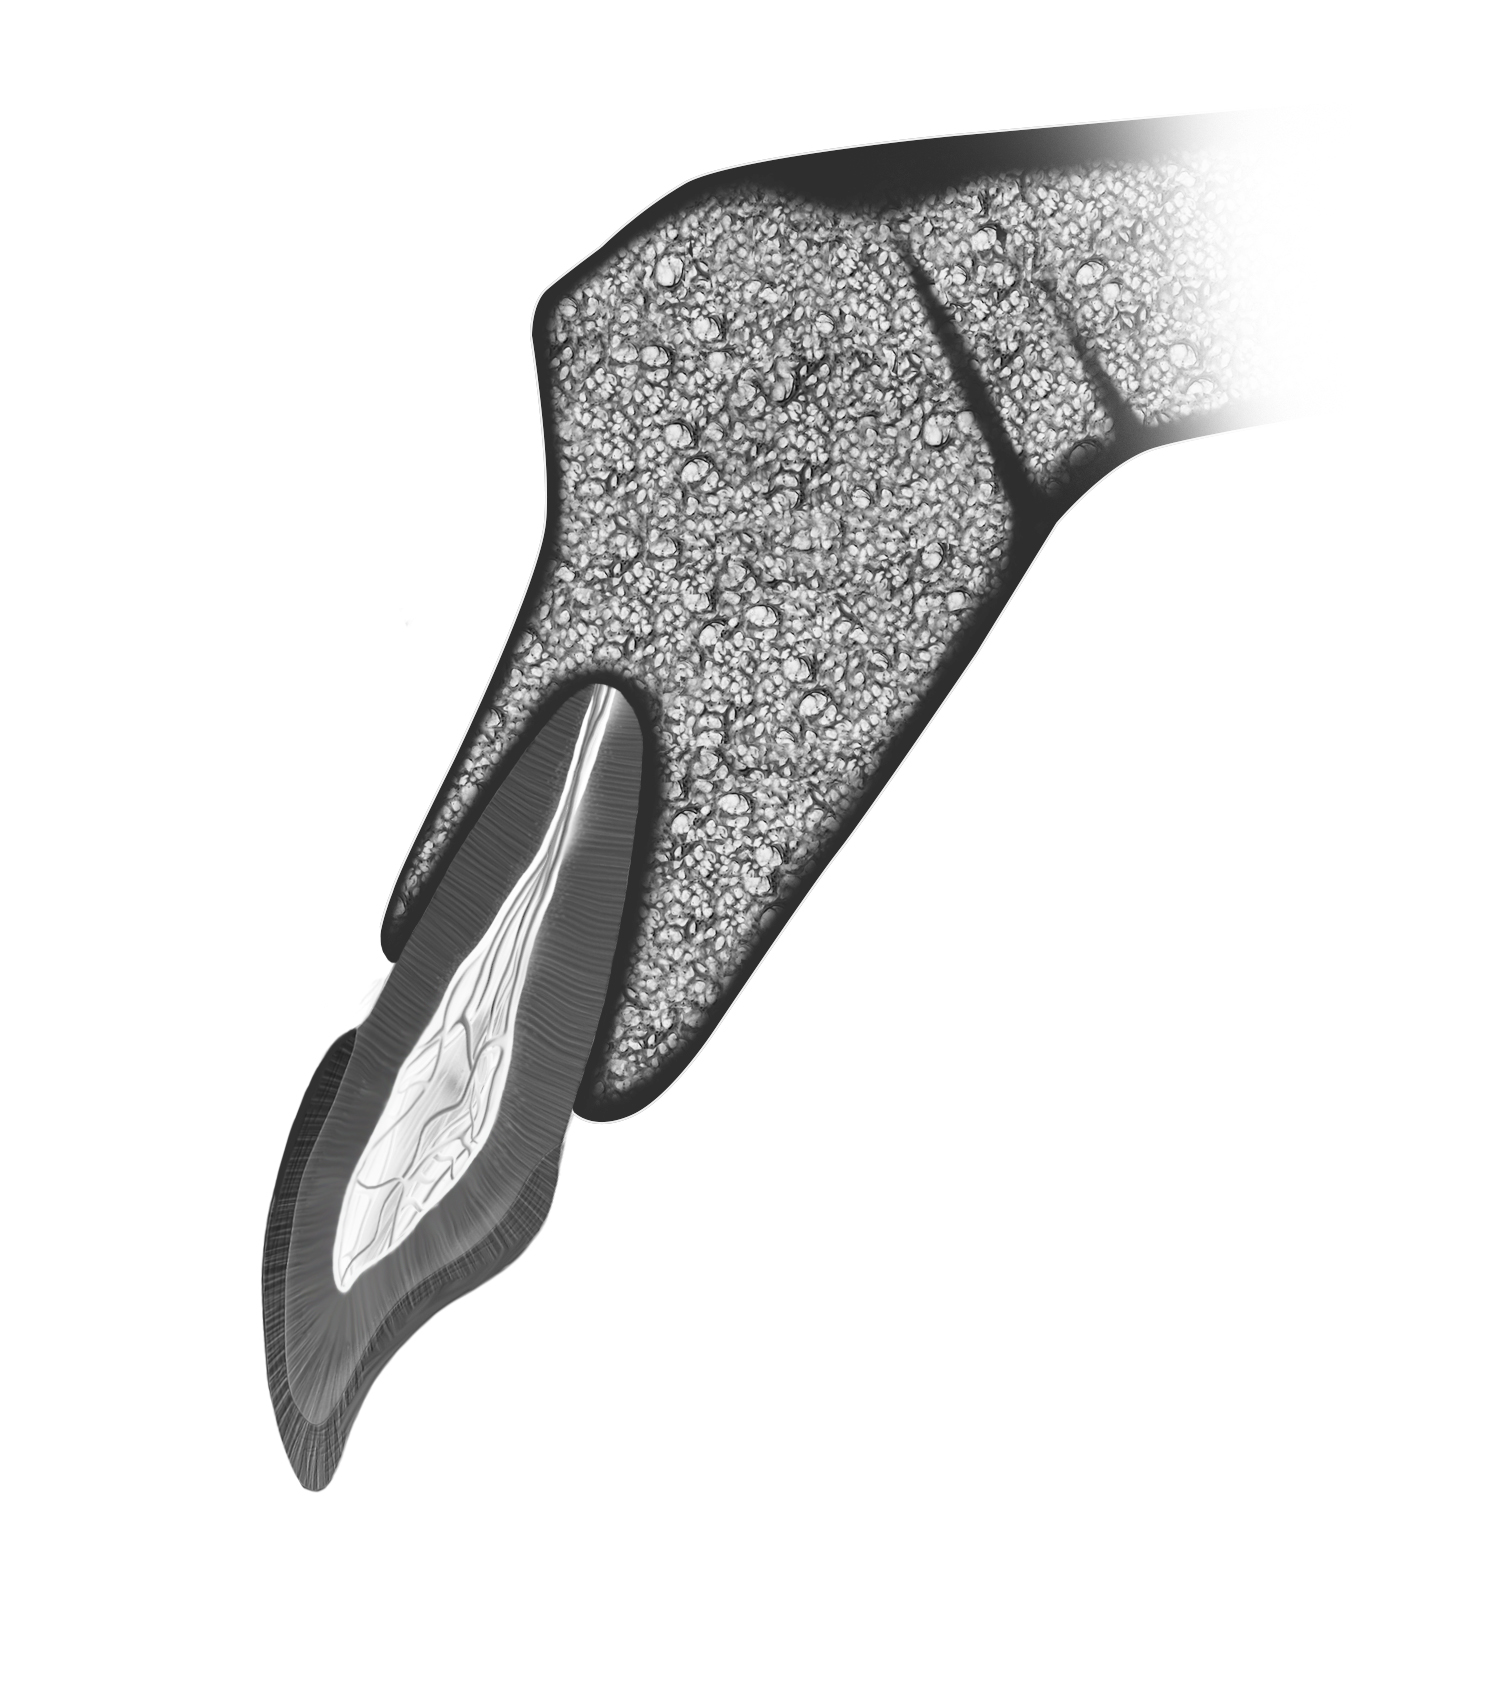

The human alveolus is an intricate, nonuniform structure that encases the complex anatomy of the human dentition and critical anatomic landmarks. Teeth, particularly those in the anterior, display a slight disparity between root and crown angulations (Figure 1), imposing obstacles in implant dentistry. The replacement of lost teeth has long been a challenge. The contemporary treatment of choice in many cases is the implant-supported prosthesis (ISP), which has been in use since the discovery of osseointegration by Professor Per-Ingvar Brånemark in the 1960s.1 An osseointegrated implant provides a direct and relatively rigid connection of the implant to the bone.2 Careful surgery is required to place a titanium fixture in the correct 3-dimensional position in bone to support an esthetic and functional tooth replacement.

Kan et al9 showed that in 76% to 86.5% of cases, the tooth position in the anterior maxilla is most often positioned very close to the buccal plate (Figure 1). This plate and the roots are proclined forward from the nasal spine. Consequently, together with the crown–root angulation offset, a straight implant fixture is unlikely to be able to fully satisfy both root and crown positions, particularly if the prosthesis is to be screw retained.

Fig 1. The most common position of the tooth in the anterior maxilla, with the root in intimate contact with the buccal cortical plate. Note the biaxial relationship between the tooth crown and root.

Figure 1

Fig 3. Root-to-crown offset of 8 to 12 degrees for anterior teeth.

Figure 3

Howes et al40 described the research and development of an implant with 12-degree subcrestal angular correction, originally designed to overcome the anatomic constraints of the anterior maxilla for screw retention. In this unpublished study, the authors recognized the conflict between the surgical and restorative objectives in ISPs in the anterior maxilla. The morphology of the anterior maxilla was analyzed on lateral cephalometric radiographs of 30 class I to III maxillae. In addition, the differences between the axes of the crowns and roots of 30 anterior teeth were assessed, including canines and lateral and central incisors. The root–crown offset ranged from 8 to 12 degrees (Figure 3), and the angle between the buccal plate and ideal screw axis ranged from 25.6 to 30 degrees (Figure 4). The resultant fixture design had a 12-degree angular offset between implant body and prosthetic platform, with a 0.6-mm body thread pitch to minimize apical travel per rotation. This implant is able to accommodate these angulation constraints due to the combined taper and head angulation.